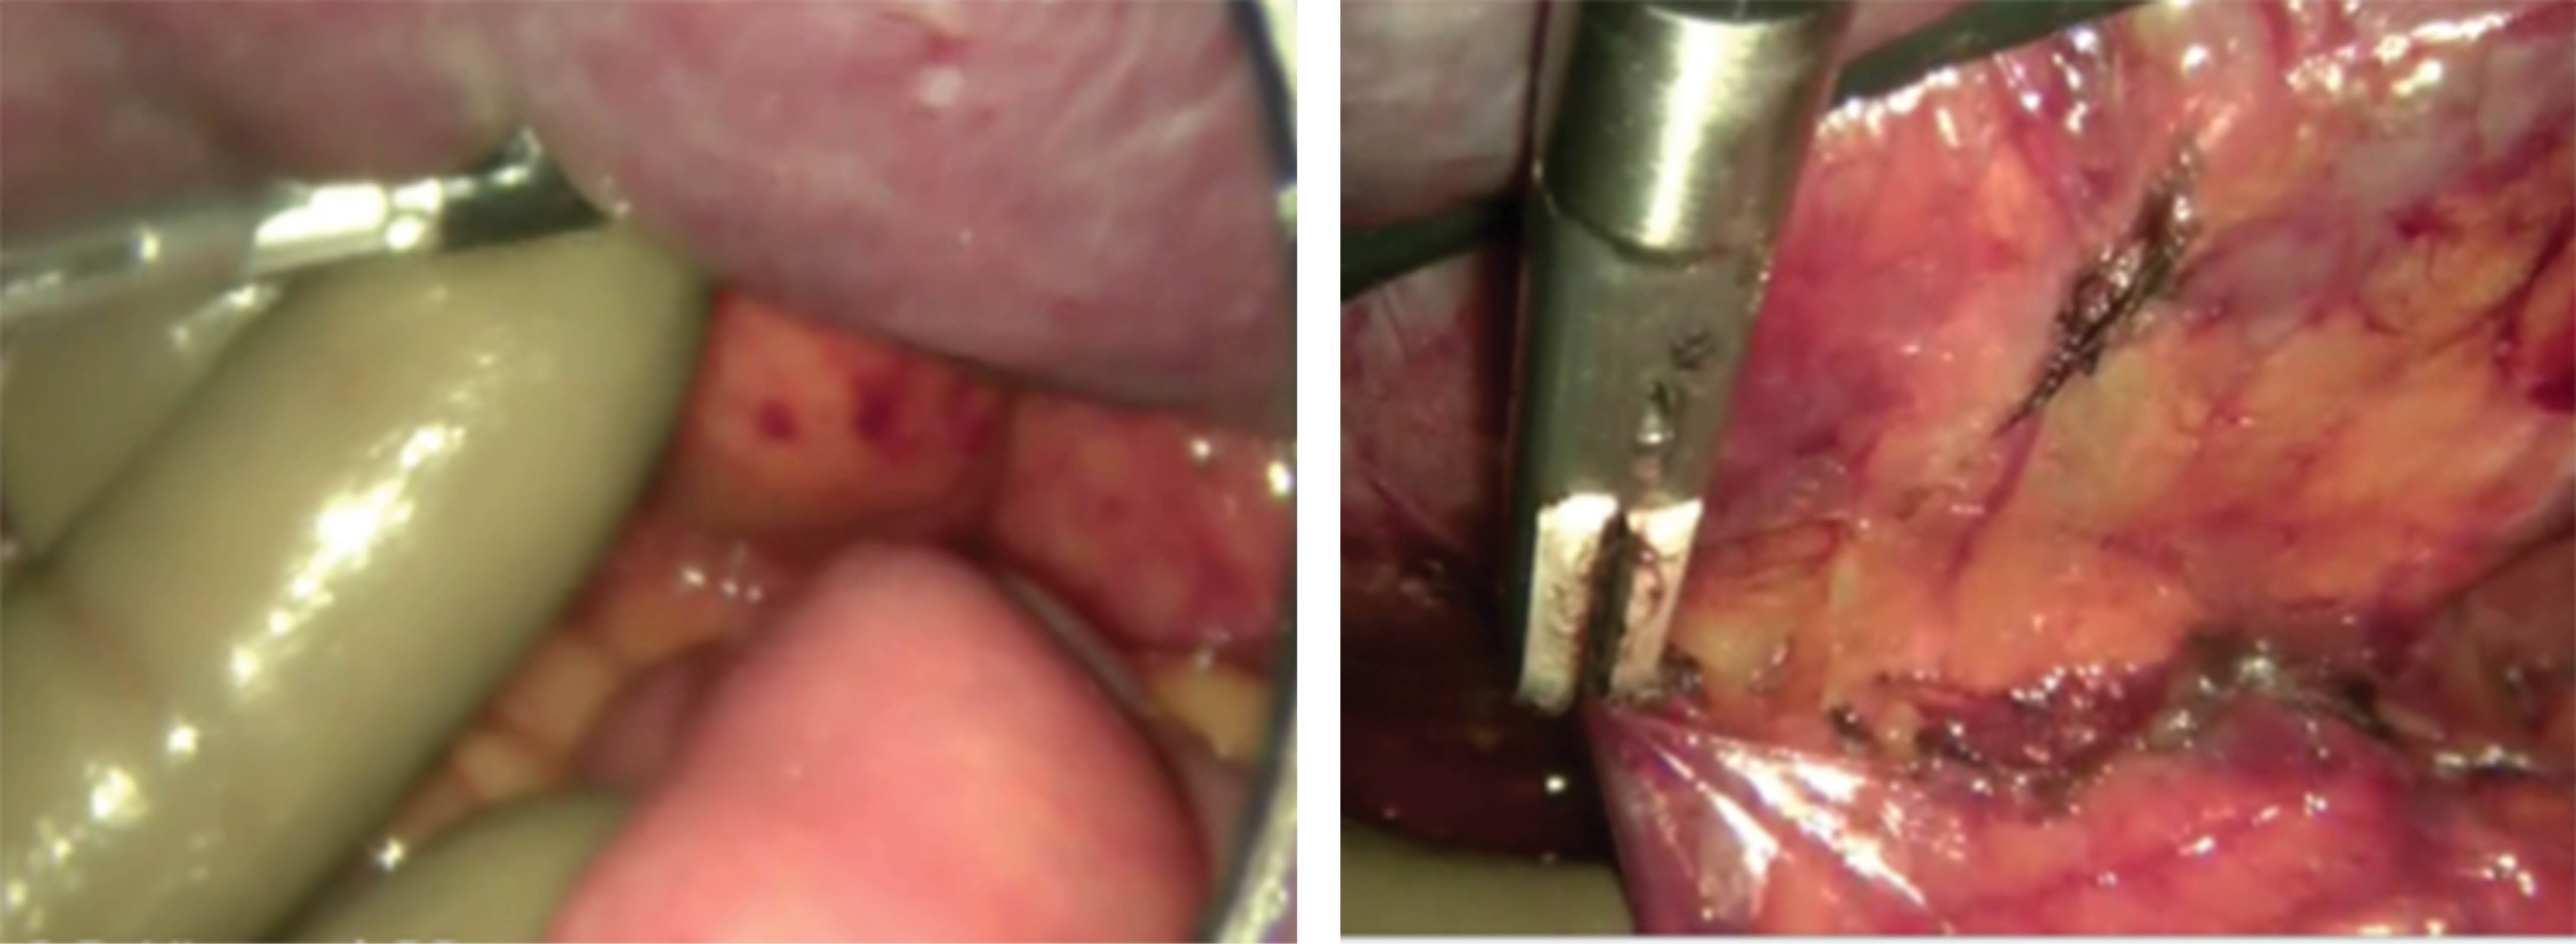

Introduction: Minimally invasive surgery has constantly evolved since the 1980's; multiple international centres have developed devices and approaches with the intention of reducing the risk of haemorrhage, postoperative pain and hospital stay, as well as improving cosmetic results. These improvements have positioned laparoscopic approach as the main option for the non – urgent splenic resection. Methods and material: The case presents a 74-year-old female with multiple comorbidities, chronic anemia and difuse abdominal pain, predominant in the upper left cuadrant; palpable splenomegaly down to the left iliac crest; US and CT shows a 20 × 17 × 8 cm spleen, with a calculated volume of 1400 cm3. Hand-assisted laparoscopic approach is performed through 3 ports; vascular control with endostapler, finding a 25 × 15 × 10 cm spleen. Results: Satisfactory postoperative evolution and patient discharge at day 4 with significant haemoglobin rise and cese of abdominal pain. Conclusion: Integral selection and meeting of criteria in patients with massive splenomegalia, improves the surgical treatment. Hand-assisted laparoscopic splenectomy (HALS) is a viable option, which allows an optimized movility of the spleen and adjacent structures and which reduce the risk of surgical convertion to open surgery, less associated morbility and still preserves the benefits of minimally invasive surgery.

Figure 2